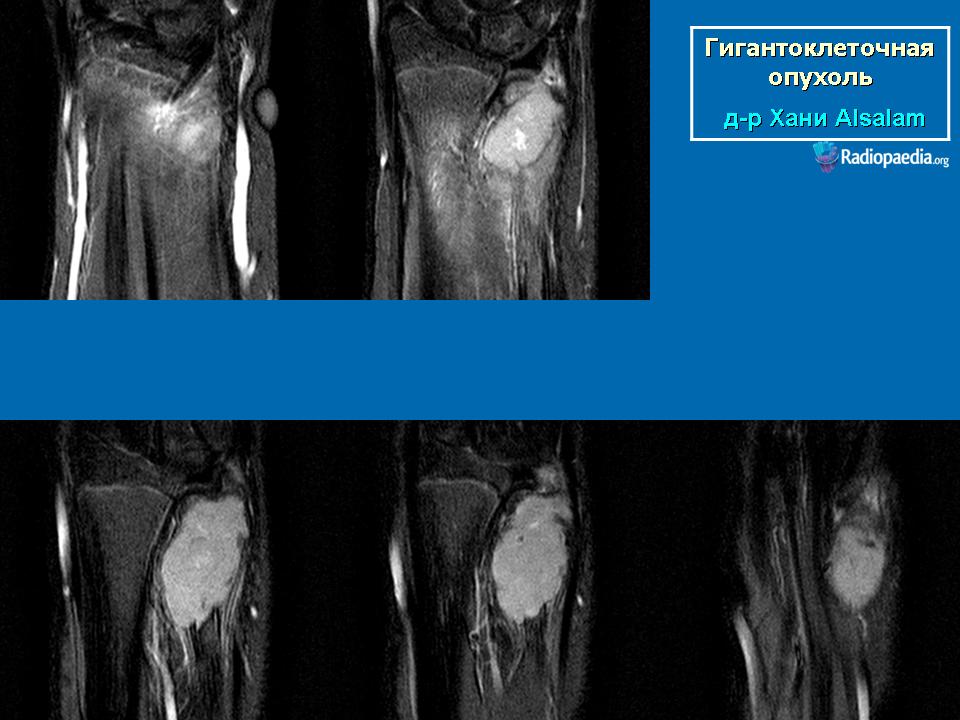

С Радиопедии.

1.c4c3a0942939fa09989865228b6e63_jumbo.jpeg2.eff1f6af4a4427cf606a2a3ab6f965_jumbo.jpeg3.6fd0e87a7ffe8_jumbo.jpeg11.19b7f328f48583d74178c58625c6a9_big_gallery.jpeg12.a1acd4f1a146afe69f8347a6e35258_big_gallery.jpeg13.921919eff44a24fa88de0840b3f171_big_gallery.jpeg14.23f5a1f56cfa5338_big_gallery.jpeg15.e0dab0c23d678f4337b9a1e139ecc6_big_gallery.jpeg21.5f0e4a8dc1e4a94d56f310c0a5167f_big_gallery.jpeg22.a6b61d25e0b665746f3c0d6cd63016_big_gallery.jpeg23.0257387bcf44029a9c23e64dae6ab8_big_gallery.jpeg24.ff425558b8c1ebe2efc93d097c2cf6_big_gallery.jpeg258f123374a0ff9c7a5e44b3bde7878c_big_gallery.jpeg2636ee626acb7ae3c10fd274781352cd_big_gallery.jpeg27.1f65f2348e83c3c694c2c98f253061_big_gallery.jpeg